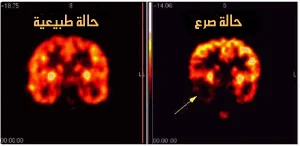

عُرف صرع الفص الصدغي TLE في عام 1985 من قبل الإتحاد الدولي ضد الصرع ILAE على أنه حالة تتميز بنوبات متكررة تنشأ بشكل غير مفهوم عن جزئين في الدماغ هما الفص الصدغي وقاع البطين Hippocampus الذي يشبه فرس البحر، كما هو موضح في الصورة.

يكون قاع البطين مسؤولاً عن عمليات التعلم والذاكرة بينما مناطق الفص الصدغي الموجودة أعلى الأذنين والممتدة حتى خلف الرأس تكون مسؤولة عن الذكريات والتذكر والعواطف ولها دور أيضاً في عملية النطق والسماع والإدراك (أي كيف نرى العالم من حولنا).